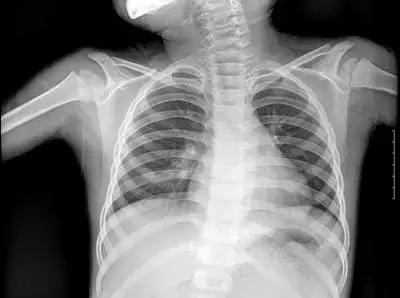

但人体各组织结构的密度不同,X线穿透时被吸收的量不同,就形成了黑白灰分明、层次显著的“片子”。看图举例子:

▲X射线成像图

骨骼、钙化灶、体内液体等(听起来质地较厚重的组织),吸收X光较多,因此形成白色影像,也就是传说中的“高密度影”,上图的上臂、肋骨就是如此。

呼吸道、胃肠道、脂肪组织(听起来质地较疏松),吸收X光较少,在片子上显现黑色影像,即“低密度影”,图中含气体较多的肺脏是代表。

再就是密度居中的实质器官、 肌肉、结缔组织,比如心脏,在片子上显现的影像介于黑白两色之间。

X光片“泾渭分明”的特点帮医生辨别身体的不同病变。

骨折、肋骨病变,密度高的骨骼白色影像哪里出问题一目了然,比如液气胸等肺部及气道病变,肺脏的黑色影像中就会混入明亮的白色。